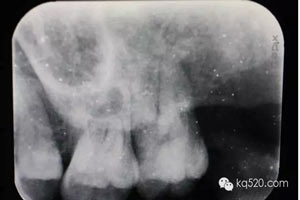

圖2.根尖片檢查:28遠中水平阻生,看不清28牙根與上頜竇的關系,建議拍全景片。

圖3.全景片影像檢查:28牙根似乎位于上頜竇內(nèi),拔除28要注意上頜竇瘺。

圖15.術后拔除28的根尖片影像:27遠中根無損傷。